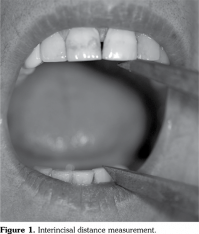

Patients were referred to the Faculty of Dentistry for the interincisal distance (ID) measurement. An experienced dentist performed the dental examination of this study. The maximal mouth opening capacity (MOC) was measured using the ID between the maxillary and mandibular central incisors in the midline as described by Wood and Branco.[19] Before measuring MOC, the subjects were asked to rest in the visiting area for at least 10 minutes. MOC was measured for each subject in the Frankfort horizontal plane (a line from the tragus of the ear through the palpable bony infraorbital rim area), which was oriented parallel to the floor, according to the natural head position in a dental unit. The subjects were asked to open their mouths as wide as they could with no pain. The linear distance from the incisal edge of the upper central incisor to the incisal edge of the lower central incisor was recorded using a dental bow compass and measured with a millimeter ruler. Each subject was measured three times every two minutes and the highest value of these three measurements was recorded (Figure 1).[20]